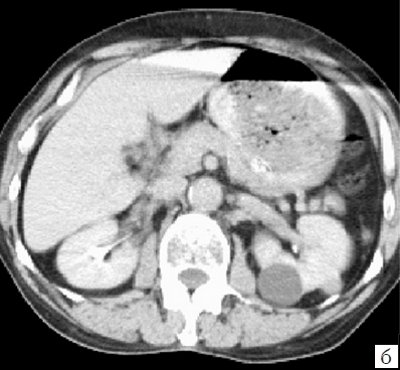

Простая киста почки при КТ визуализируется как гомогенное округлое образование без видимой капсулы, четко отграниченное от нормальной паренхимы. Образование имеет однородную, относительно низкую плотность, соответствующую плотности воды (0…+20Н). При КТ с внутривенным усилением плотность, размеры и форма образования не изменяются (рис. 2).

а) До контрастирования определяются три гомогенных округлых образования с четкими ровными контурами, без видимой капсулы, однородной плотности, характерной для воды.

б) После введения контрастного вещества кисты не изменяют форму, размеры и плотность.

Компьютерная томография. В нижнем полюсе левой почки определяется гомогенное образование с четкими контурами, округлой формы, однородное по эхоструктуре, без признаков капсулы, четко отграничена от нормальной паренхимы, с равномерно пониженной плотностью изображения до +7 HU по шкале Хаундсвильда, диаметр 50 мм. После введения контрастного вещества образование не меняет свою форму, размеры и плотность.

Заключение: Киста I категории в проекции нижнего полюса левой почки (рис. 4).

а) До контрастирования.

б) После введения контрастного вещества.